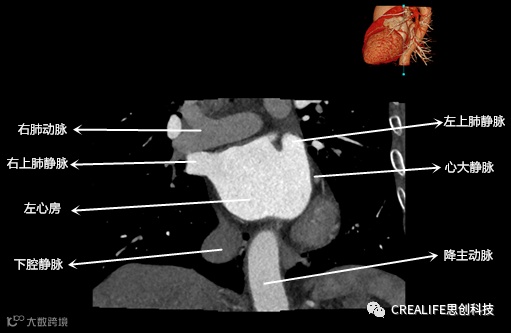

今天,跟大家分享心脏影像的经典层面——冠状位。通过冠状位的影像,我们可以从正位观察到心脏结构,看到主动脉的纵向剖面及冠窦交界处的心脏形态等多方位的心脏结构。现在,就让我们率先一睹“冠状位”的奇妙风采吧!

毋庸置疑,影像解剖学可为医师提供优良的诊断依据,包括瓣膜钙化程度、主动脉瓣环直径、主动脉窦直径及高度、冠状动脉开口高度、入径血管直径等关键数据,以此,为术前提供更全面的评估指标。